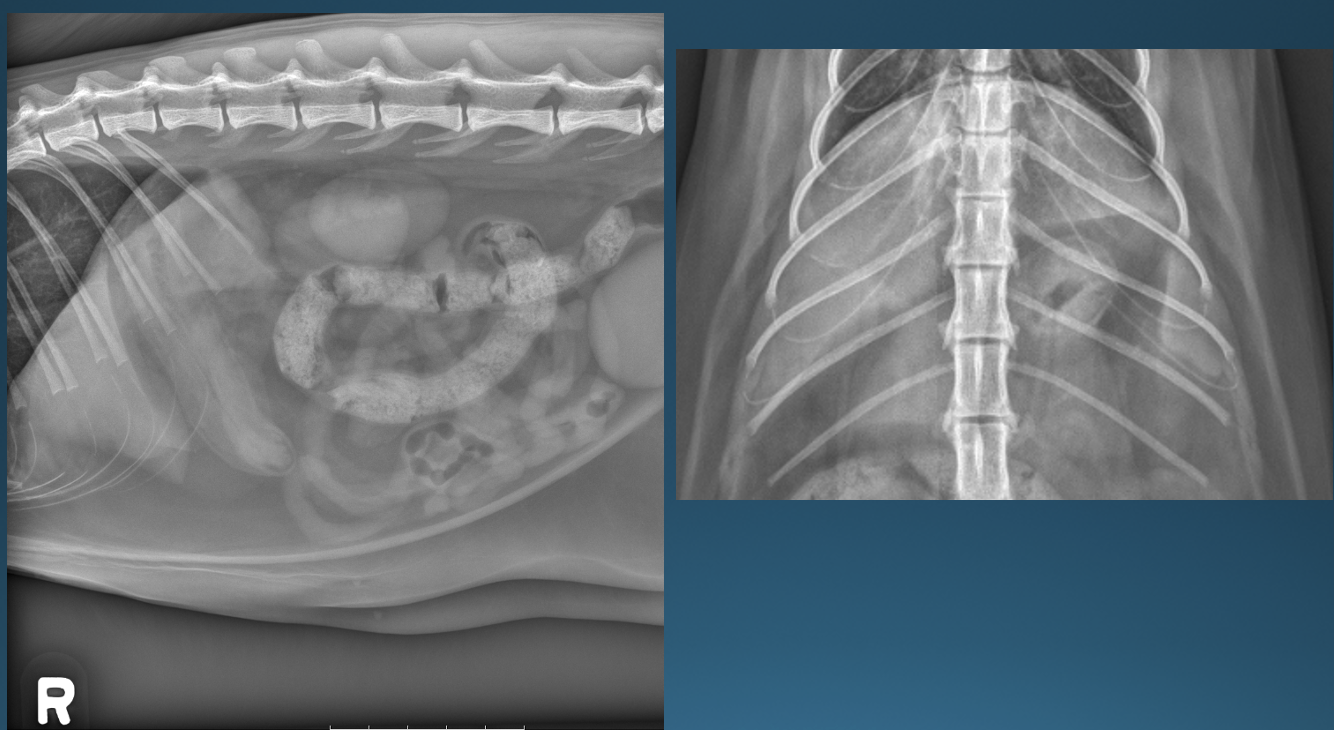

What is shown in these images?

A

normal feline stomach